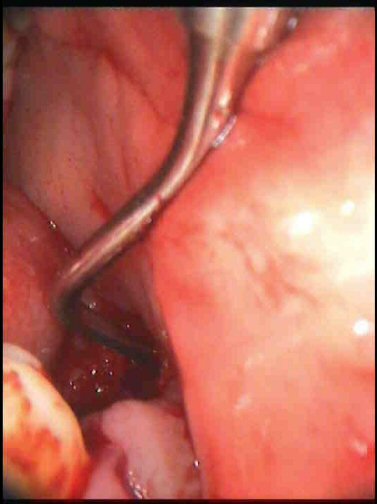

On the left side, they also found a rather large hole. This is the opening to it.

When they opened this side up, a terrible smell was released, they had found the infection ! The infection had entirely destroyed the bone under the adjacent tooth, and part of the bone around the next tooth. What used to be healthy bone, had turned into a sort of mushy jelly. This is some of what they cut out of my jaw. It's not a great picture but you can just about see it.

This jelly stuff they cut out of my jaw, I had seen it before. When I first had the operation to extract my wisdom tooth on the left side, the dentist removed a lot of what looked exactly like that. The dentist thoroughly cleaned out the area, and cut enough bone away to hopefully stimulate healing, then stitched me up.